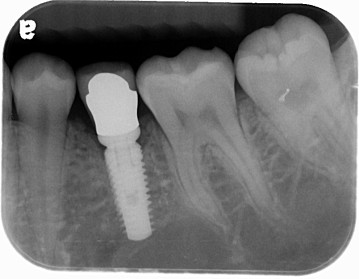

患者許小姐,左下第二小臼齒,因為深度蛀牙,因而牙齒被拔除(圖一、圖二、圖三),患者由於是一位高二學生,深怕缺牙久了若不處理,鄰牙可能倒過來(圖四),但若以傳統假牙修復,還需再磨完整的自然牙(圖五),經轉診至本診所尋求人工植牙。

圖二 |